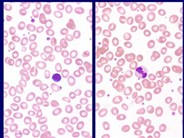

Atypical megakaryocytes

Many atypical megakaryocytes are seen characterized by small size, hypolobated or non-lobated nuclei, and often plasmacytoid appearance with eccentric nuclei. Erythropoiesis and granulopoiesis are relatively unremarkable. Blasts are not increased.